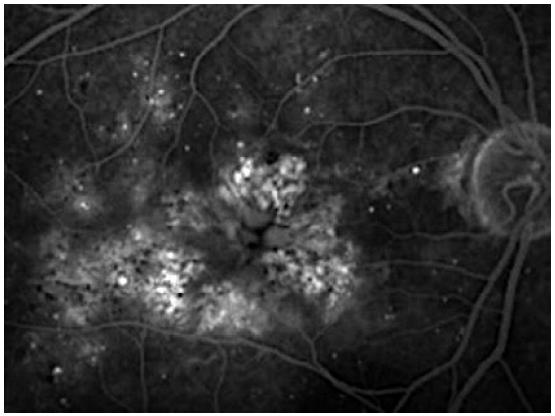

Дифференциальная диагностика отека макулы, развивающегося после хирургии катаракты у больных СД, вызывает значительные трудности, так как две формы отека (ДМО и КМО) могут присутствовать как самостоятельно, так и в комбинации. КМО на ФАГ проявляется накоплением флуоресцеина в перифовеальной области в виде лепестков с/без окрашивания диска зрительного нерва (рис. 2) [19]. При ДМО на ФАГ наблюдают просачивание флуоресцеина из микроаневризм, участки ишемии сетчатки. Как правило, микроаневризмы окружены отложениями твердых экссудатов (рис. 3) [20].

Рис. 3. Кистозный макулярный отек по данным флуоресцентной ангиографии.